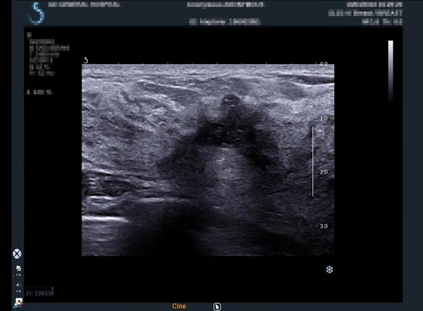

Ultrasonography is an important routine examination for breast cancer diagnosis, due to its non-invasive, radiation-free and low-cost properties. However, it is still not the first-line screening test for breast cancer due to its inherent limitations. It would be a tremendous success if we can precisely diagnose breast cancer by breast ultrasound images (BUS). Many learning-based computer-aided diagnostic methods have been proposed to achieve breast cancer diagnosis/lesion classification. However, most of them require a pre-define ROI and then classify the lesion inside the ROI. Conventional classification backbones, such as VGG16 and ResNet50, can achieve promising classification results with no ROI requirement. But these models lack interpretability, thus restricting their use in clinical practice. In this study, we propose a novel ROI-free model for breast cancer diagnosis in ultrasound images with interpretable feature representations. We leverage the anatomical prior knowledge that malignant and benign tumors have different spatial relationships between different tissue layers, and propose a HoVer-Transformer to formulate this prior knowledge. The proposed HoVer-Trans block extracts the inter- and intra-layer spatial information horizontally and vertically. We conduct and release an open dataset GDPH&GYFYY for breast cancer diagnosis in BUS. The proposed model is evaluated in three datasets by comparing with four CNN-based models and two vision transformer models via a five-fold cross validation. It achieves state-of-the-art classification performance with the best model interpretability.

翻译:超声波分析是乳腺癌诊断的一个重要常规检查,原因是其非侵入性、无辐射和低成本的特性。然而,由于其内在局限性,它仍不是乳腺癌的第一线筛选测试。如果我们能够精确地通过乳房超声图像诊断乳腺癌(BUS),它将是一个巨大的成功。我们提出了许多基于学习的计算机辅助诊断方法,以实现乳腺癌诊断/感官分类。然而,其中多数方法需要事先确定性能模型,然后对ROI内部的跨值进行分类。常规分类支柱,如VGG16和ResNet50等,可以在没有ROI要求的情况下实现有希望的分类结果。但是这些模型缺乏可解释性,从而限制了其在临床实践中的使用。在本研究中,我们提出了一个新的无乳腺癌诊断模型,在超声波图像中进行解释性特征描述。我们利用了先前的解剖学学学知识,即恶性肿瘤和良性肿瘤模型在不同组织层之间有着不同的空间关系,并提议采用状态解析法来编制这一先前的知识。拟议中的HOVer-Trans-Trading-Tradef-trainal Ex-deal-dealal-deal-deal-deal-degraphal-deal-deal-deal-deal-deal-deal disal disal-dal-dal-dal-dal-dal-deal-deal-dal-deal-deal-deal-dal-dal-dal-dal-dal-dal-dal-dal-dal-dal-dal-dal-dal-dal-I-dal-Iversal-dal-Ial-d-d-I-d-d-I-I-I-I-I-I-I-I-I-I-I-I-I-I-I-I-I-I-I-I-I-I-I-I-I-Ial-I-Ial-Ial-I-I-I-I-I-I-I-I-I-I-I-I-I-I-I-I-I-I-I-I-I-I-I-I-I-I-I-I-I-I-I-I-